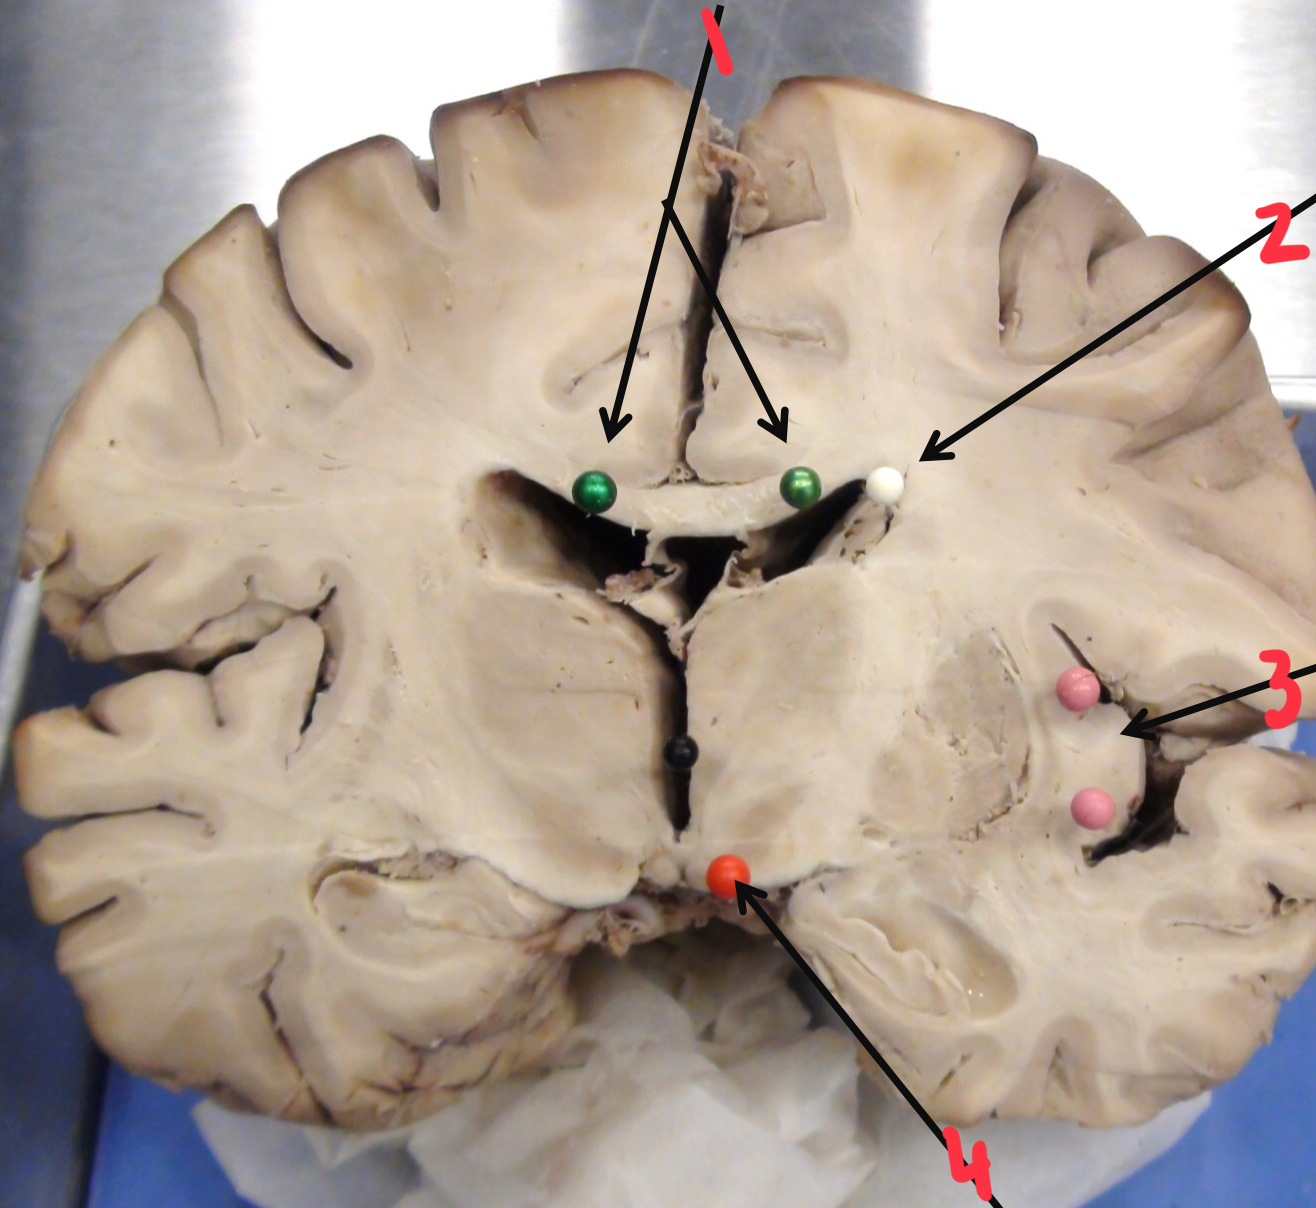

1

insula (island of Reil)

2

caudate nucleus

3

fornix

4

anterior (frontal) horn of the lateral ventricle

5

corpus callosum